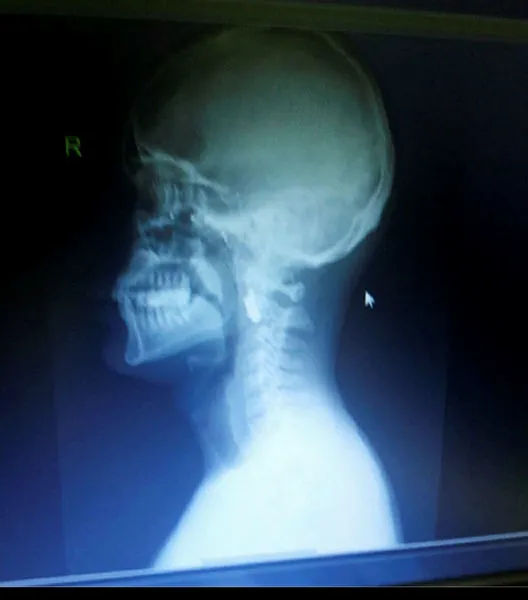

O gece İBB'nin Saraçhane'deki binasının önünde başından vurulan ve sağ gözünü kaybeden Acur'un ise kurşun tam şahdamarının yanına saplandı. O da 5 yıldır o kurşunu taşıyor.

Boynumda, şahdamarımın hemen yanı başında bir şeref madalyası var. Bu benim için öyle kutsal bir şey ki, değerini kelimelerle ifade edemem. Milletimizin, vatanımızın hürriyet belgesi bu.